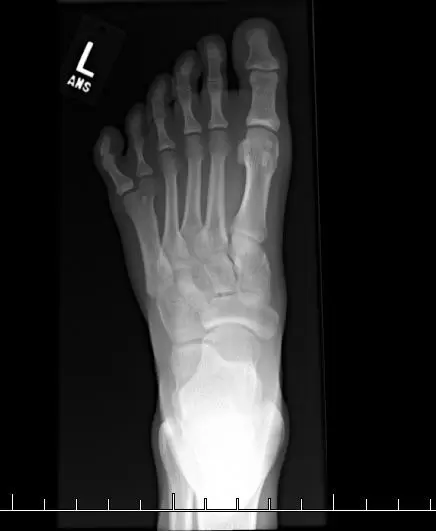

▼某位網友有六隻腳趾,X光照片顯示的模樣如下

圖片來自:buzzfeed